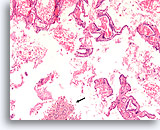

Afbeelding 65

Papillair schildkliercarcinoom, schildklier FNA, celblok.

De aanwezigheid van overvloedig colloïde sluit een papillair schildkliercarcinoom niet uit.

10X

Afbeelding 65

Papillair schildkliercarcinoom, schildklier FNA, celblok.

De aanwezigheid van overvloedig colloïde sluit een papillair schildkliercarcinoom niet uit.

10X